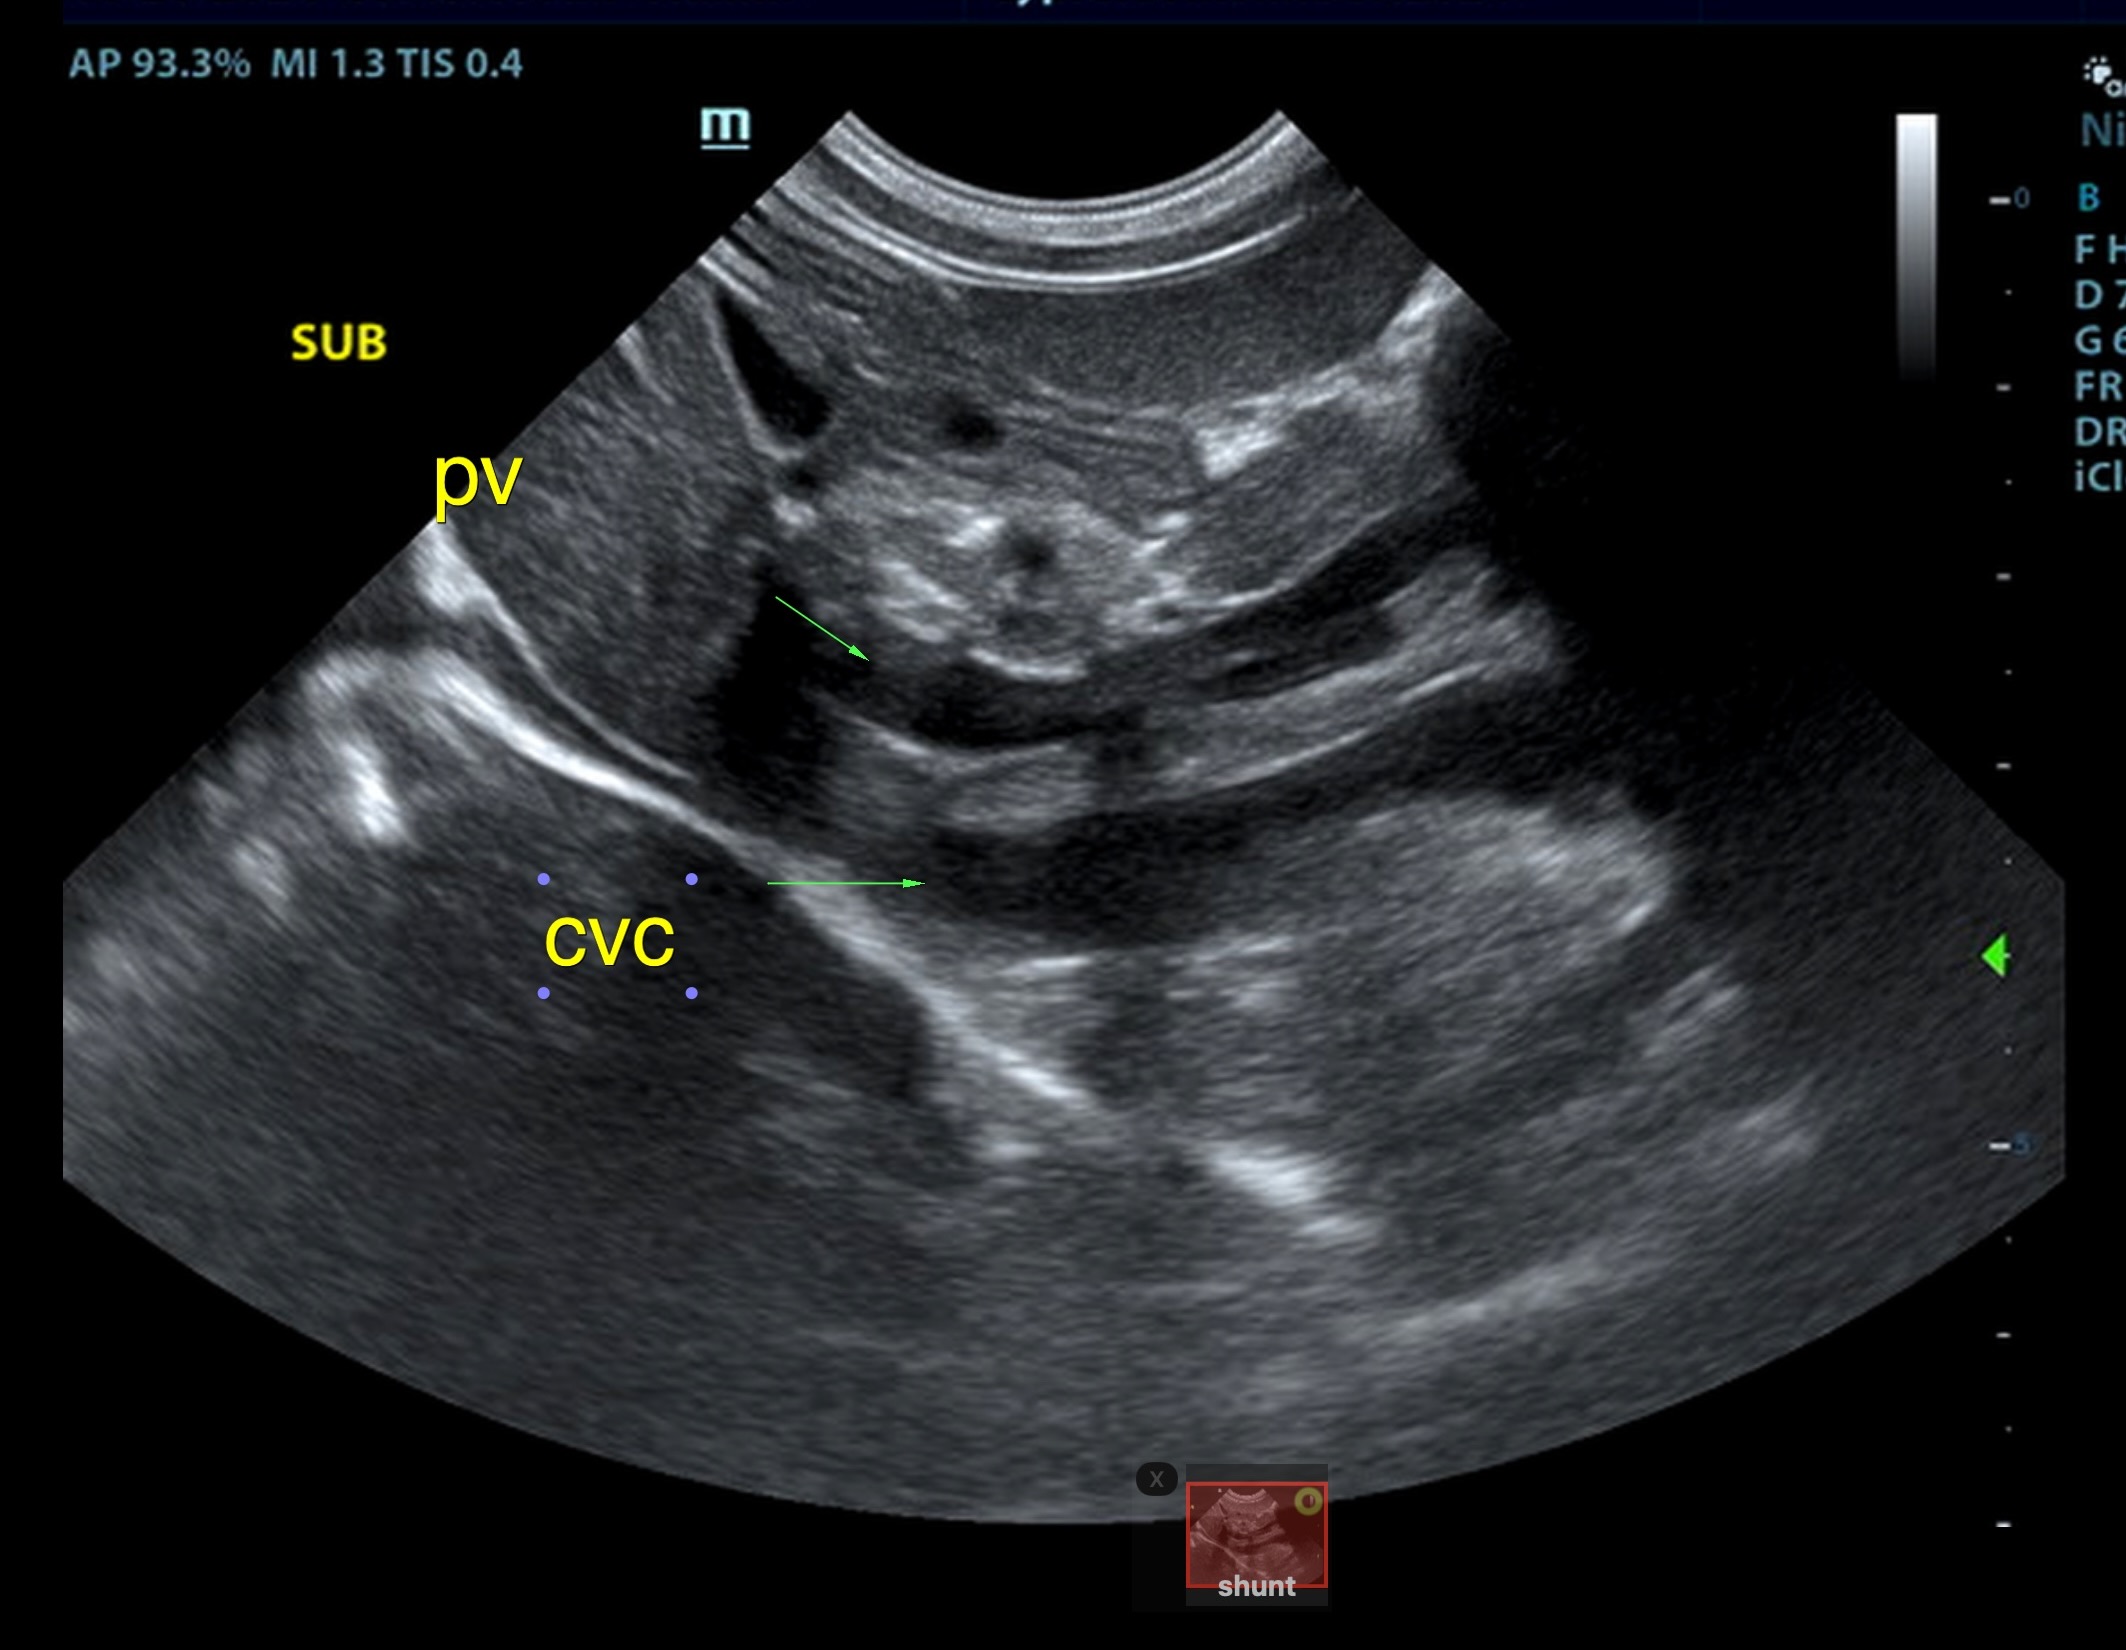

The liver was subnormal in size, yet the portal vein and vena cava ratio was 1:1. The portal veins were subnormal in size and measured 0.34 cm. The vena cava was enlarged and measured 0.34 cm. The vena cava was enlarged and measured 0.72 cm, aorta measured 0.4 cm. The branching of the portal vein appeared to be normal and of adequate volume. The portal vein and vena cava measured 0.5 cm each in the extrahepatic space. The splenic vein entry into the portal vein and gastroduodenal vein entry into the portal vein appear to be normal. There was one turbulent vessel in the region of the central branch of the portal vein, which may represent an intrahepatic shunt, but this could not be confirmed. The width of the shunt is approximately 0.76 cm. This is in position of central divisional shunt; however, right divisional origin cannot be completely ruled out. The gallbladder presented acceptably thin walls with primarily anechoic content. The cystic and common bile ducts were normal.